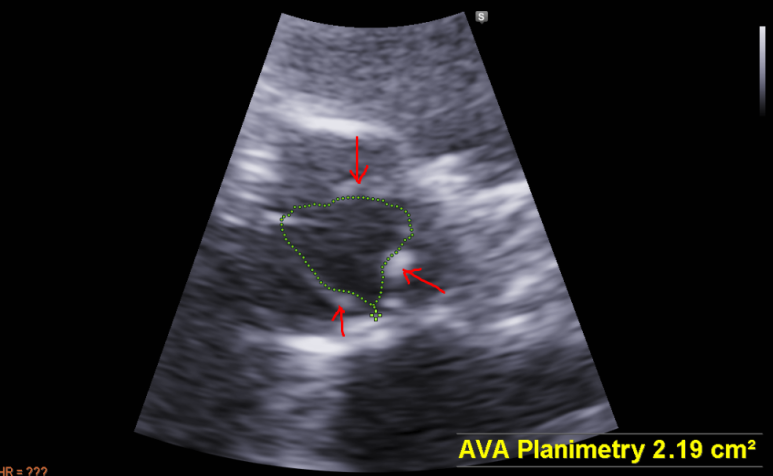

영상에서 대동맥판 경화증 관찰되어 폐쇄 여부 확인, 대동맥판에서 나가는 혈류는 정상 범위, 경도의 역류소견이 CW 도플러에서 관찰

대동막판 면적은 정상범위

경화성 변화 (적색 화살표)